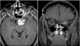

Optic nerve sheath meningioma

Optic nerve sheath meningiomas (ONSM) are rare benign tumors of the optic nerve. 60–70% of cases occur in middle age females, and is more common in older adults (mean age 44.7 years). [Source: Wikipedia ]